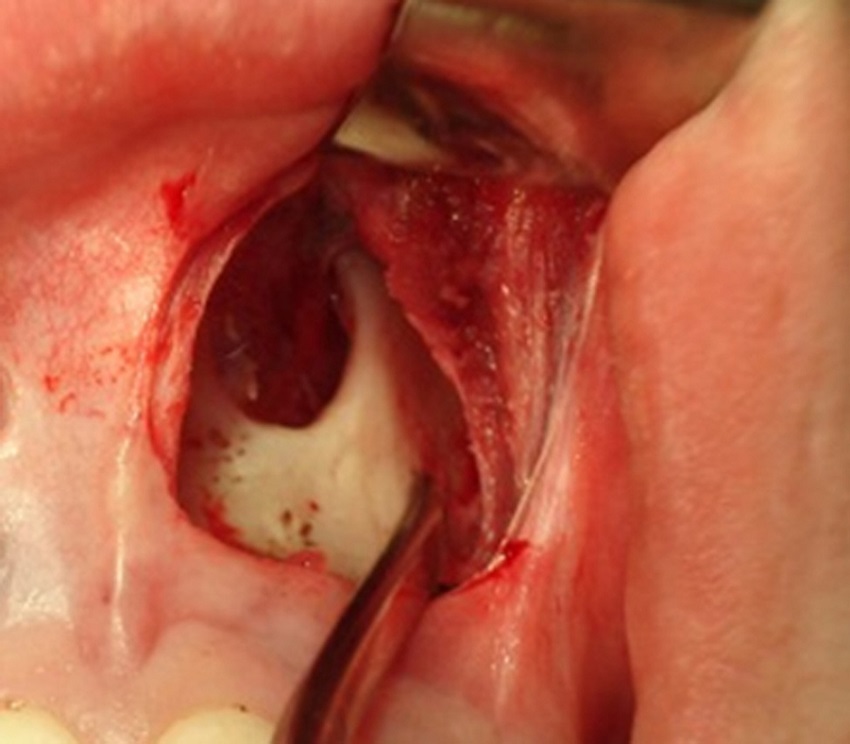

Surgical technique

Three months after being submitted to surgery, the patients returned and answered the NOSE questionnaire, to the same examiner, and were submitted to postoperative rhinomanometry with the same equipment, with and without vasoconstrictor agent.